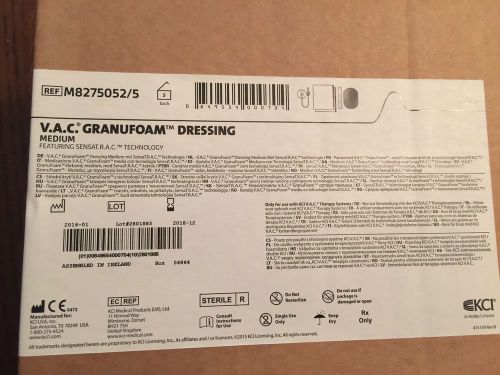

300ml Canister (with Gel) for ActiV.A.C. Therapy System by KCI Ref M8275058 (3)

KCI VAC THERAPY SENSA T.R.A.C. PAD & V.A.C DRAPE STERILE WOUND M8275067 (14) pcs

M8275052/5 GranuFoam Medium KCI Dressing Box of Five Pieces

V.A.C. White FOAM DRESSING - SMALL - KCI WOUND VAC Therapy - LOT of 6 *SEALED!